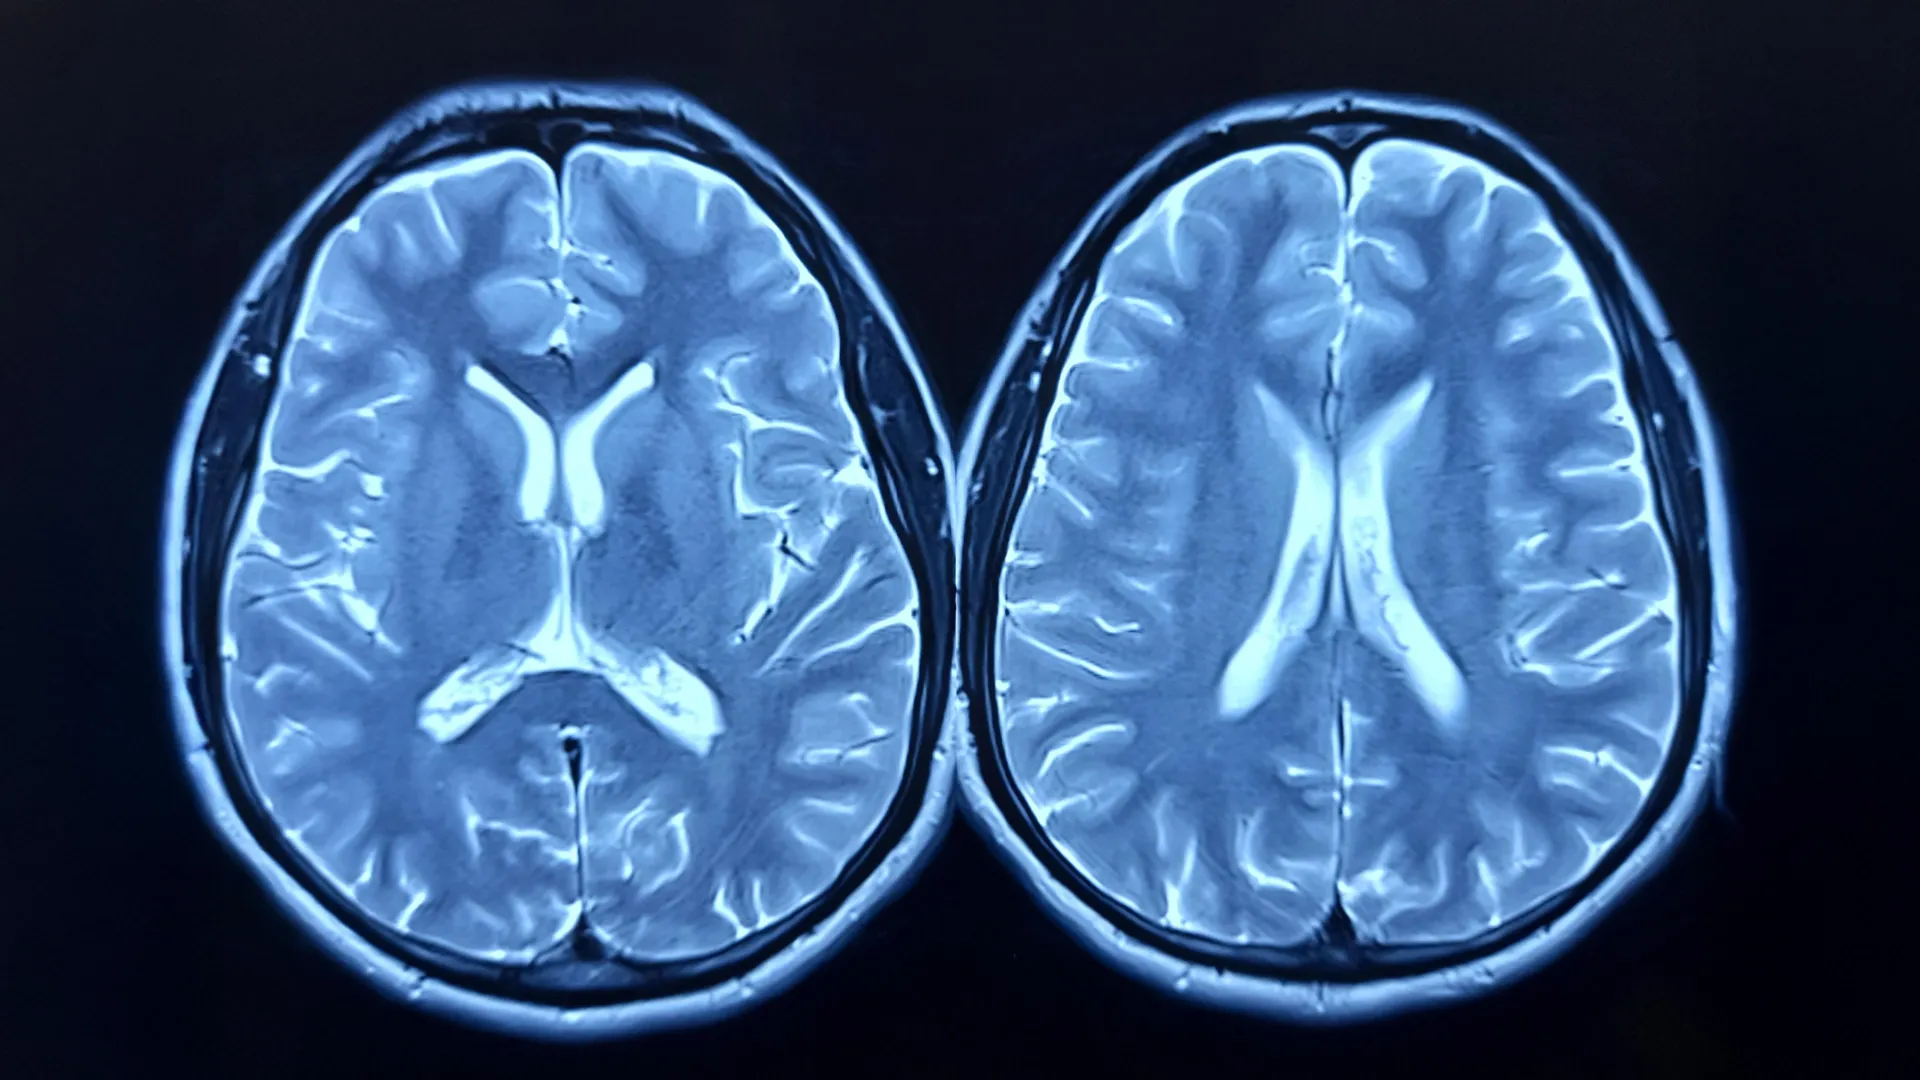

The research team looked at longitudinal brain scans from nearly 1,000 healthy adults, taken as part of the UK Biobank study. Some participants had scans before and after the pandemic; others, only before. Using advanced imaging and machine learning, the researchers estimated each person’s “brain age” — how old their brain appeared to be compared to their actual age.

The brain age model was developed using brain scans from over 15,000 healthy individuals, without comorbidities, allowing the researchers to build an accurate model for estimating brain age.

Stamatios Sotiropoulos, Professor of Computational Neuroimaging, and co-lead author added: “The longitudinal MRI data acquired before and after the pandemic from the UK Biobank gave us a rare window to observe how major life events can affect the brain.”